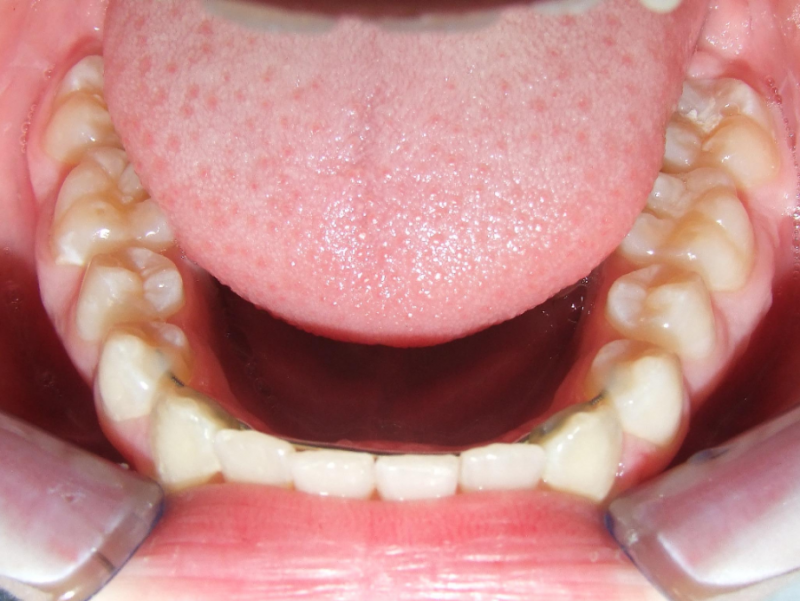

eindfoto

Beschrijving

Leeftijd bij aanvang: 10 jaar

Bonded Hyrax + volledig vast onderkaak

Volledig vast bovenkaak + expander

Wrap + c-c bar onderkaak

Leeftijd bij afname: 12 jaar